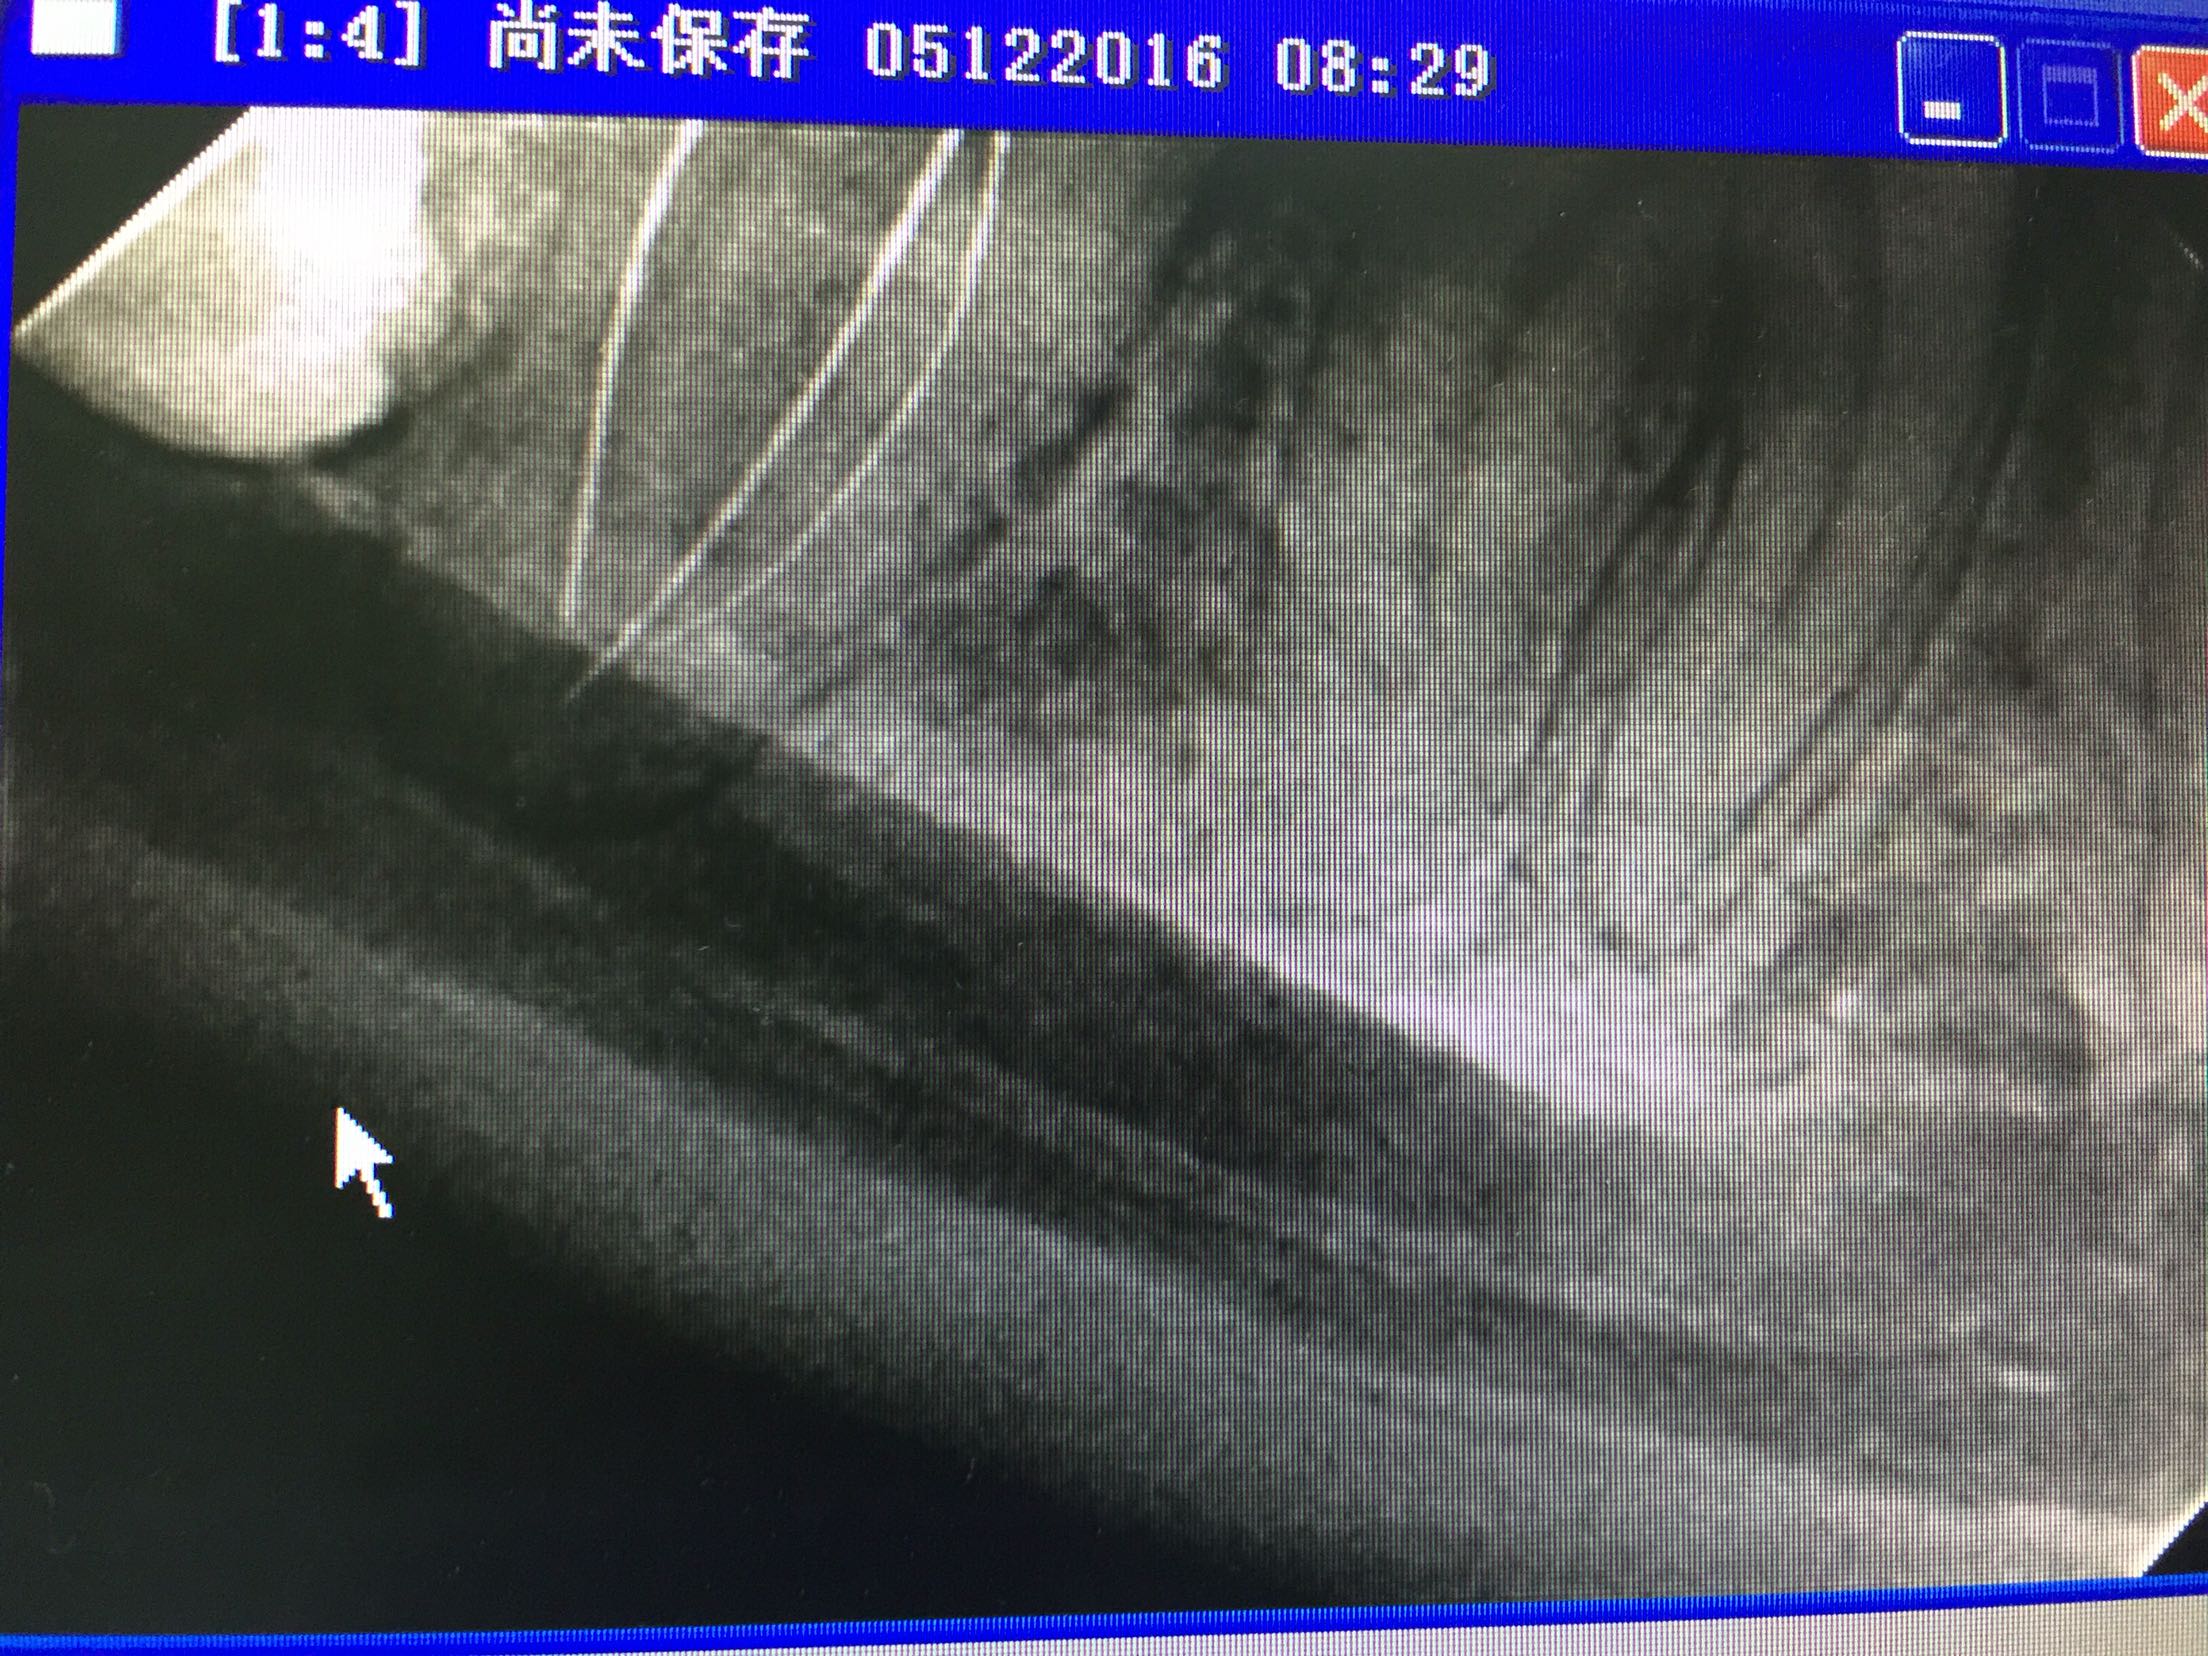

检查:47颊合面深龋,探及穿髓点,探诊(+),叩诊(+-),松动不明显,牙龈无明显红肿,冷诊(++)。辅查:47合面低密度影像及髓。

诊断:47牙髓炎 治疗:47局麻下去龋净,开髓揭顶全,拔髓,疏通根管,根管中上段预备,长度测量,waveone根管预备,1%次氯酸钠冲洗,试尖,干燥,根管封药,告医嘱,肿痛随诊? 复诊无不适。47去暂封及根管封药,终末冲洗,干燥,根充,适充,锌基,树脂充填,调合,抛光,告医嘱,建议择期冠修复。